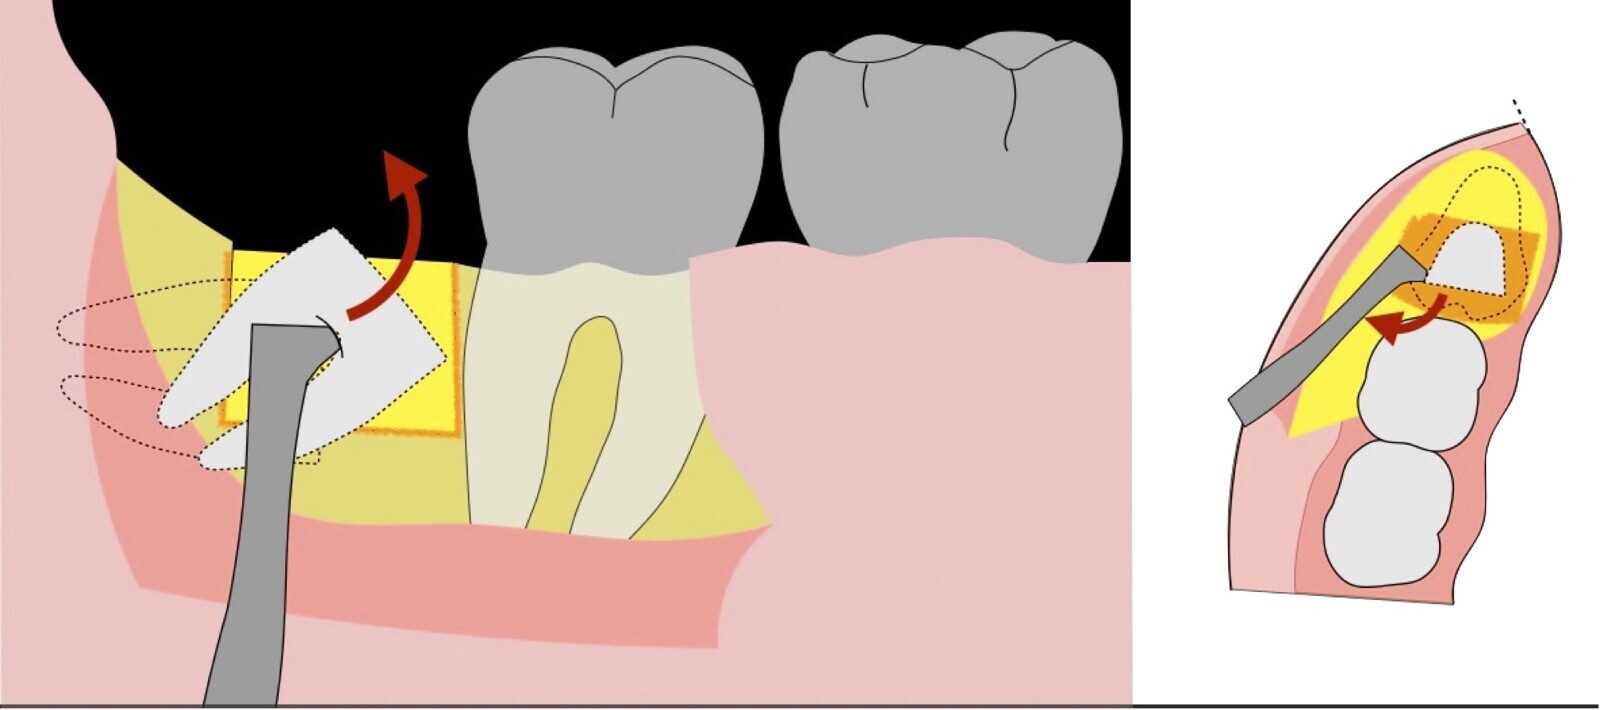

Figura 5. Fractura y eliminación oclusal del fragmento óseo de la porción coronal oclusal.

Figura 6. Demarcación y fractura de la zona de osteotomía a nivel vestibular con inserto aserrado recto y/o angulado.

Figura 7. Eliminación del fragmento vestibular.